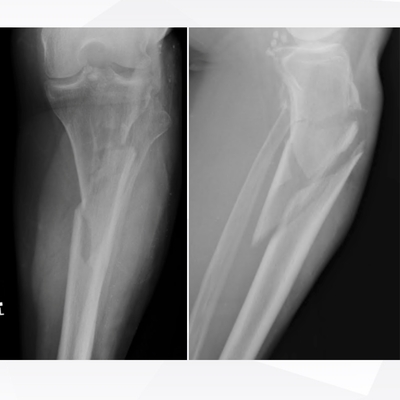

Click on an image below to view more info.